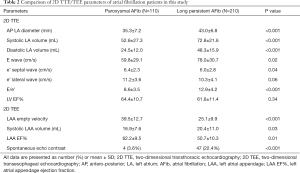

2D TTE and 2D TEE echocardiography results

The 2D TTE and 2D TEE left atrial and LAA images were collected from all patients. The 2D TTE and 2D TEE features of the enrolled patients are shown in Table 2. The average anteroposterior (AP) diameter of the left atrium in paroxysmal AFib patients by 2D TTE was 35.3±7.2 mm, compared with 43.0±6.8 mm in the long-standing AFib group (P<0.001). The systolic and diastolic average left atrial mean volume (biplane) were 52.6±27.3 and 24.5±12.0 mL, respectively, in the paroxysmal patients, compared with 72.8±21.6 and 48.3±15.9 mL, respectively, in the long-standing AFib group, and these differences were statistically significant (P<0.001). In most long-standing AFib patients, the anterior blood flow Doppler modality presented as unimodal. The results were statistically significant in terms of the value of E wave value, e’ septal wave, and E/e’ ratio. However, between the two study groups, there was no difference in terms of the LVEF value (P=0.34).

Full table

We also obtained good quality LAA images by 2D TEE in all patients, and LAA morphology and functional parameters were accurately collected. We found that long-standing AFib patients had a persistent dysfunctional LAA with a lower empty velocity (LAAeV) (mean value 25.1±9.9 cm/s) and lower LAA EF% (mean value 50.7%±10.3%) compared with the paroxysmal group, and the differences were statistically significant (LAAeV P<0.001, LAA EF% P=0.01). In addition, 2D TEE could easily observe a SEC in 51 patients (from both groups), whereas using the 2D TTE method, it was difficult to detect a SEC signal. Using 2D TEE, SEC was detected in four patients in the paroxysmal AFib group, and in 47 in long-standing AFib patients, and these differences were statistically significant (P<0.001) (Table 2).